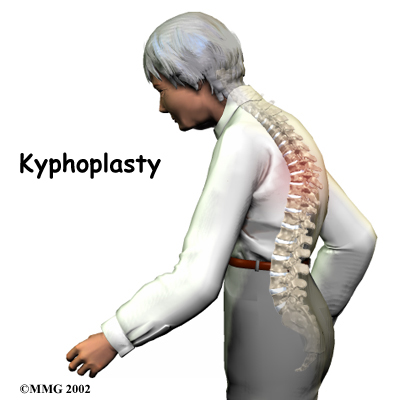

The fracture angles the spine forward and produces a hunchbacked appearance, called kyphosis. Patients with this condition are subject to debilitating pain, disturbed sleep, decreased lung and intestinal function, and difficulty completing routine activities.

Kyphoplasty restores the size and strength of the fractured vertebra. This realigns the spine and reduces pain. Nearly 95 percent of patients get immediate relief of pain with this procedure.

The main section of each spine vertebra is a large, round structure called a vertebral body. Compression fractures cause the front portion of this round bone to collapse in height. Because the back section of the bone stays intact, the damaged vertebral body becomes wedge-shaped. It is this wedge shape that angles the spine forward into kyphosis. The vertebral body is the main structure treated in the kyphoplasty procedure.

The goal of kyphoplasty is to return the fractured vertebra as close as possible to its normal height. This is done by inflating a balloon inside the fractured bone to restore the vertebral body to its normal size. Special cement is then injected into the bone, fixing it in place. The cement strengthens the broken vertebra and stiffens it in its original height and position. This reduces pain and spine deformity (kyphosis), enabling patients to get back to normal activities.